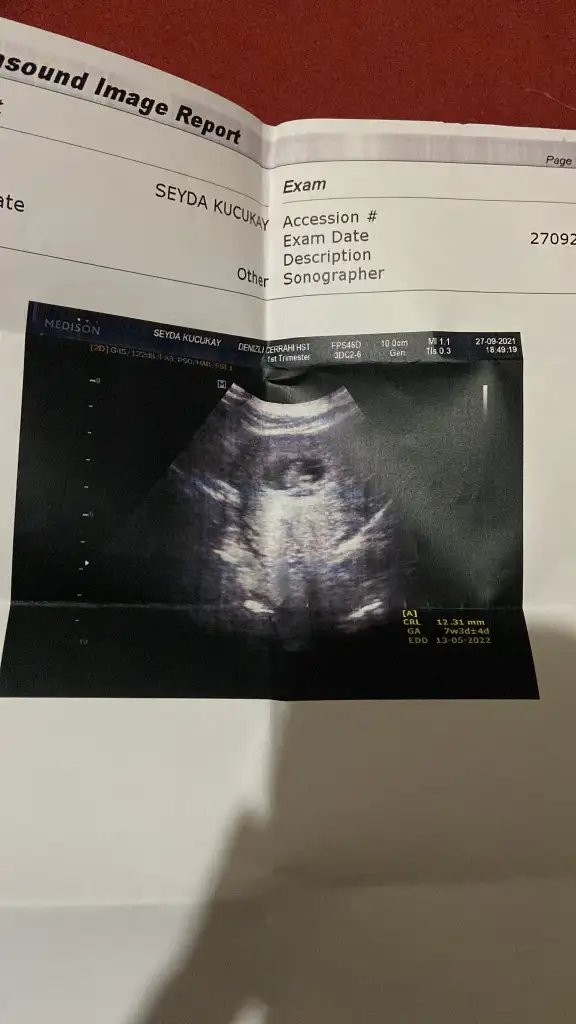

Karından , tahminde bulunabilir misinTabiki 7 8 haftalik ultrason kagidi varsa at alttan mi ustten mi soyle tahmin yapayim canim

Erkek gibi canım bence6+1 haftalık görüntü cevap verebilecek olan var mıdır?karından ultrason